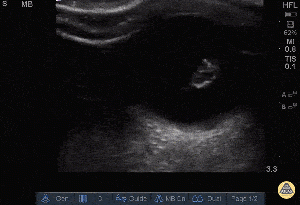

Normal

- Lens

- Vitreous chamber

- Optic nerve